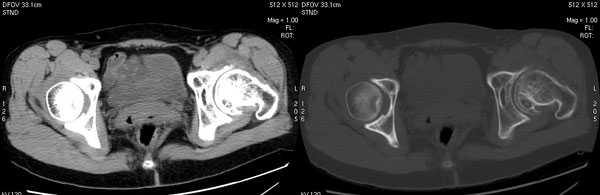

以下是引用jiajie在2006-7-14 17:19:00的发言:[br]ct所见:双侧髋关节不对称,左侧关节间隙变窄,关节面毛糙。左侧股骨头变形、无明显变小,前上缘与髋臼融合,融合处骨质明显增生硬化,并见数个小囊变影。股骨头下端与股骨颈交界部见囊样变,邻近肌肉内见囊样密度减低区,ct值24hu。右侧髋关节形态未见异常。[br][br]ct诊断:左侧髋关节结核可能,请结合临床资料进一步分析。

以下是引用lihuuuu在2006-12-5 10:14:00的发言:[br]定位像示:左侧髋臼变浅,倾斜度加大,髋臼外上缘呈波浪状不规则,骨质增生硬化,髋关节上缘间隙明显变窄,股骨头向外上轻度移位。轴位像示:左侧股骨头变形,前上缘与髋臼融合,融合处骨质明显增生硬化,并见数个小囊变影。股骨头下端与股骨颈交界部见囊样变,邻近肌肉内见密度减低区,ct值24hu,内缘见弧形高密度钙化影。右侧髋关节形态未见异常。[br]ct诊断:左侧髋臼发育不良[br] 左侧股骨头缺血性坏死[br] 左侧肌肉内低密度影伴有高密度钙化-考虑早期骨化性肌炎[br] [br]“我认为在描述上已经写了肌肉部分,印象诊断里应该写主见”[br]